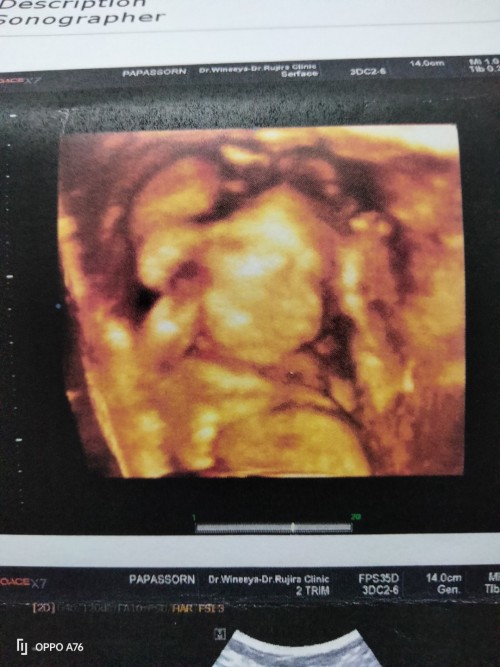

อยากเห็นใบซาวด์ทีมพฤศจิ😍

มาอวดกันเร็ววว🥰🥰 บ้านนี้13 พฤศจิ